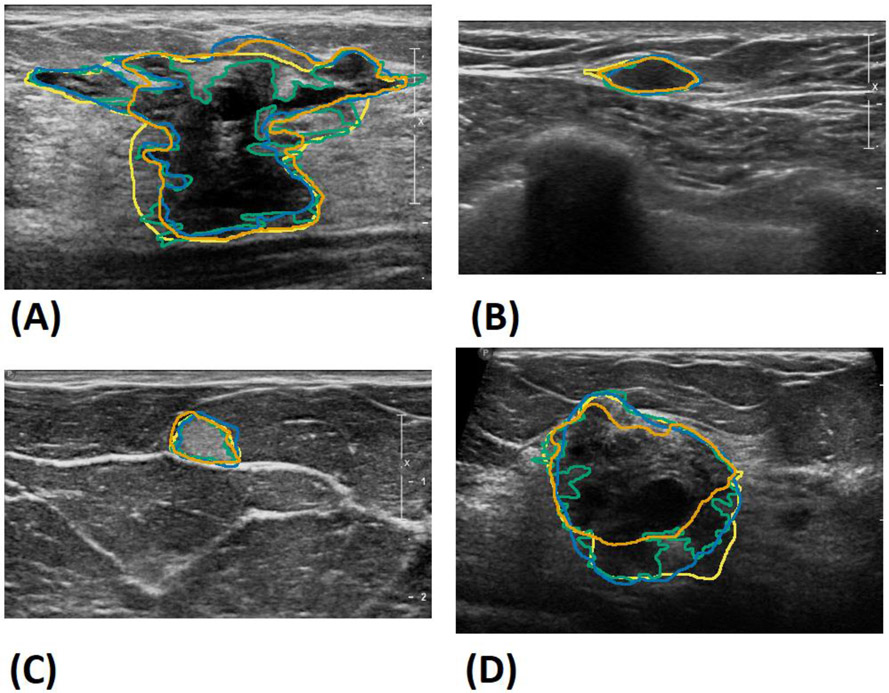

Fig.5.

Sample segmentations of all observers from the test set. A) Benign complex sclerosing lesion, B) benign fibromatosis, C) benign mastitis, D) malignant invasive mammary carcinoma with mixed ductal and lobular features. The deep learning model’s results are shown in orange, and observers 1, 2 and 3’s results are in green, blue and yellow, respectively.

Figure 3 shows the box plots comparing the performance of the experts evaluated against each other and the model compared to the experts. A small increase in the overall performance was observed in the deep learning model compared to the experts. This suggests that the model’s segmentation is a kind of “mean” between the three observers, with fewer differences between each expert compared to the experts evaluated against each other. Figure 4 shows Bland–Altman plots showing the model results vs. the difference between each observer for the segmentation area, major axis length, and minor axis length. The mean performance is very close to zero, suggesting a close agreement between the model and the experts. Result segmentations from the model are shown in Figure 5 along with the segmentations of the other observers. Figure 5A shows a benign complex sclerosing lesion with a radial scar with large and small projections. The model fails to capture a large projection on the left side, while capturing a similar projection on the right side. The model follows small projections but is not as finely segmented as that achieved by observer 1 or 2. Figures 5B and 5C show hyperechoic and hypoechoic lesions with close agreement between all observers. Previously, a modified Unet model utilizing 10 unique instances to create a consensus prediction failed to segment hypoechoic lesions, either due to their relative rarity in the training set or the overall resemblance to background echotexture [12]. Figure 5D shows an example where the model undersegments the lower edge of a lesion, perhaps failing to distinguish the boundary from shadowing.